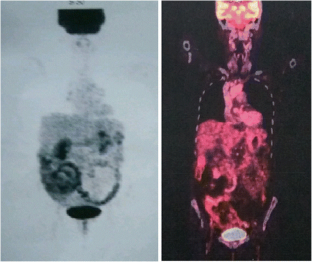

Fig. 2